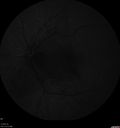

64 year old female: She woke up with a blurry area in the vision of the left eye. She was concerned (she has been in the optical business for 36 years). Her ophthalmologist asked her to come back for a visual field and then she had trouble finding someone on her insurance. Diagnosed at age 10 with RA (juvenille idiopathic). She is now doing a little better. She is now weaning off the prednisone very slowly (now on 3 mg per day). She has no eye pain and no pain on eye motion. She does have headaches which are the same as her usual headaches. 3-4 days prior to the vision loss in the left eye she did have an intermittent fever and upset stomach. She was helping with her sons cats a few months ago. She also felt neck pain and swollen lymph nodes around the back of her neck. VA OD: Dcc20/20 NccJ1 VA OS: Dcc20/160 NccJ16-1 Bartonellas IgG was very positive - IgM negative (this is true about 50 percent of cases) Her vision returned to 20/25 within about 2 months

Neuroretinitis and Multifocal Retinitis424 views62 year old female with vision loss in the left eye to 20/160. Positive Bartonellas IgG. Vision recovered in 2 months. She was treated with Oral Erythromycin BID for 2 weeks.00000